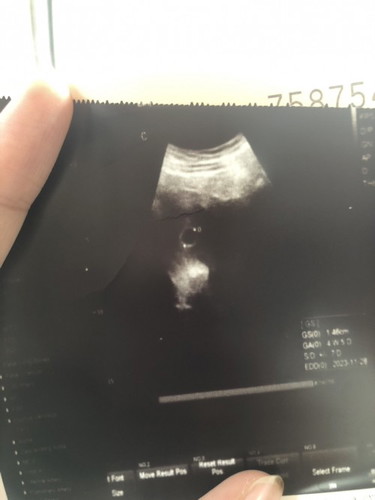

Scan baru nampak kantung . Tahun lepas miscarrige 5w 5d . Ini yang sekarang dah 3 hari keluar spotting browniesh tapi takde sakit perut . Cuma sengal2 pinggang dan punggung je . Then cepat penat . Dr kata ada dua kemungkinan , miscarrige atau early pregnancy . Harap baby baik baik saja . Dah lama teringin nak ada zuriat macam orang lain 🥹 #firstmom #firstbaby